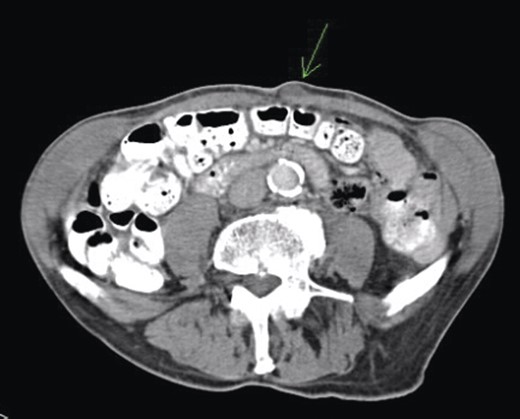

Given his previous colorectal disease, a repeat colonoscopy and computed tomography (CT) scan (Fig. 1) were arranged and the carcinoembryonic antigen (CEA) level was checked. Colonoscopy showed some thickening of the anastomosis but was otherwise unremarkable, and a CT scan showed no significant findings. CEA was raised at 11.2; therefore, excision of the lesion was done in January 2009 and following histopathological analysis, a positron emission tomography (PET) scan was arranged.